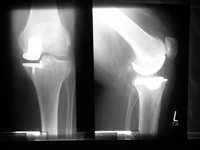

Kompletter Oberflächenersatz

Dieser Prothesentyp stellt den Standard in der Kniegelenksendoprothetik dar. Sind mehrere Teile des Kniegelenkes durch die Arthrose zerstört, müssen alle beteiligten Gelenkflächen ersetzt werden.

Bis auf wenige Ausnahmen (s.u.) kann ein Großteil der arthrotischen Kniegelenke mit diesem Prothesentyp behandelt werden.